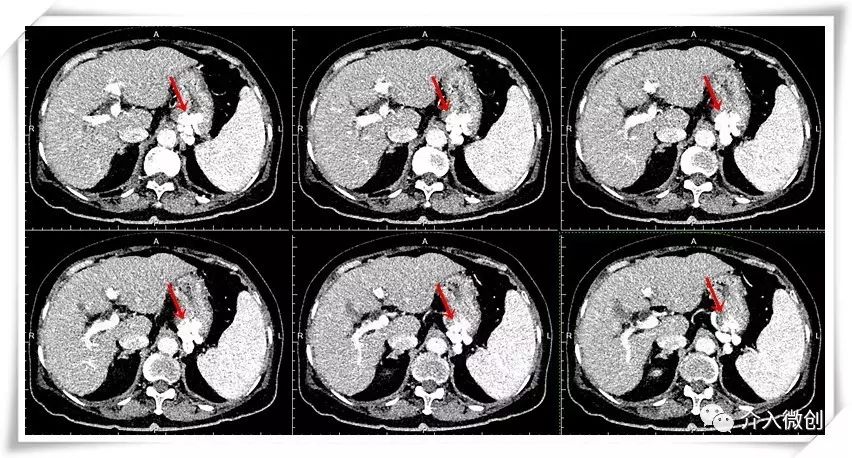

老年女性,反复出现呕血,电子胃镜检查提示胃底静脉曲张,经胃镜下曲张静脉套扎及组织胶注射治疗,仍反复出血。

- 腹部增强CT示轻度肝硬化、脾大、胃底静脉曲张。